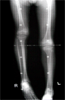

Post

Op

valgus subtrochanteric osteotomy and lengthenn distal femur